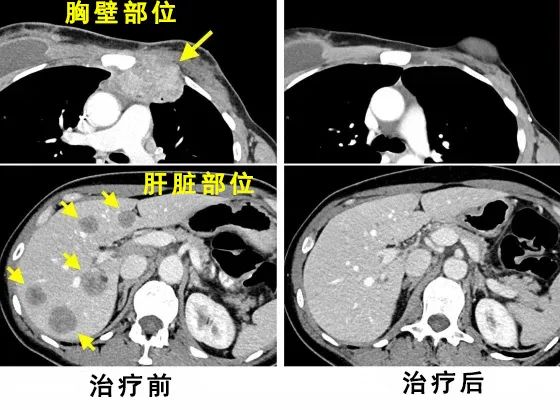

下图是乳腺癌患者朱迪·珀金斯治疗前后的病灶扫描结果[1]。

从图片中能很明显的看到,治疗后,扫描显示所有肿瘤病变均已消失。

到 2016 年 5 月,也就是她接受治疗五个月后,扫描结果显示她没有癌症,她形容这个结果是“奇迹”。